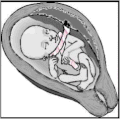

| Baby in the uterus with umbilical cord wrapped around its neck and arm | |